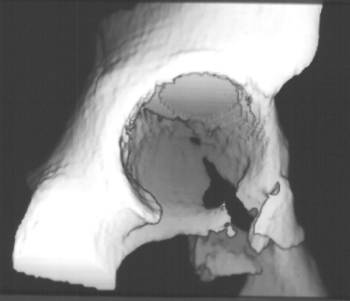

A 16 year old female was previously in good health when she was involved in a roll-over motor vehicle accident as an unrestrained passenger, and ejected from the vehicle. She landed in a field. She was taken by ambulance to a nearby hospital complaining of pain in the pelvis. An x-ray of her pelvis was obtained (image 1), Obturator and iliac oblique(image 2), A CT scan of the fracture was obtained (images 3, 4 & 5).